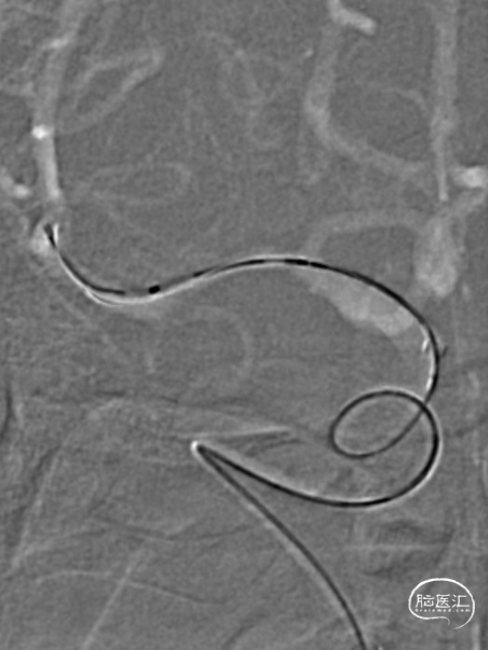

手推冒烟见RICA C1-C5段显影,C5段以远闭塞。将Pro-18微导管在Synchro(0.014×200mm)微导丝引导下送至RMCA M2段,微导管冒烟示远端血流通畅。将Trevo XP(4×20mm)取栓支架于M1段远端向RICA末端释放,采用SWIM技术取栓1次,并同时将中间导管送至颈内动脉末端抽吸。抽出数枚暗红色血栓。

造影见RICA再通,RMCA M1段近端重度狭窄,约90%。

Trevo XP ProVue 4×20mm取栓支架全程显影,能准确定位闭塞段血管,并在取栓过程通过支架形态变换间接推断局部是否狭窄病变,同时亦具有良好的血栓抓捕能力。Catalyst7中间导管跟踪到位性好,多次操作耐用,口径比Catalyst6大,更适合反复抽吸操作。